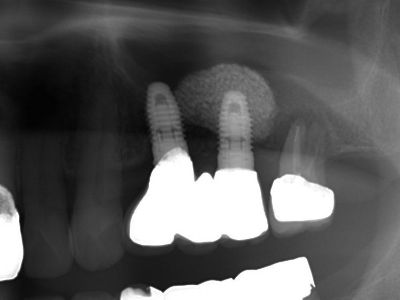

| これは、インプラントを入れた当日に仮の歯をブリッジにしていれた状態のレントゲンです。 インプラントを埋入するときのトルクが35N(ニュートン)から40Nの範囲で埋めることができないと その場で仮歯を入れて咬めるようにして帰っていただくこと(即時荷重)が出来ません。 骨がある程度硬くないと無理ですし、また、軟らかい骨でも削るのではなく押し広げるように形成することによって このトルクを作るようにします。 最初のドリルの感じで、どのように押し広げれば 適正なトルクで埋入することが出来るかがイメージ出来なければ無理です。 また、骨の幅がギリギリでシミュレーションとの誤差が0.3mm以内の精度でしかも方向を合わせなければいけません。 文字通り職人技です。 これが出来る歯科医師は、兵庫県でも極少数だと自負しております。 |